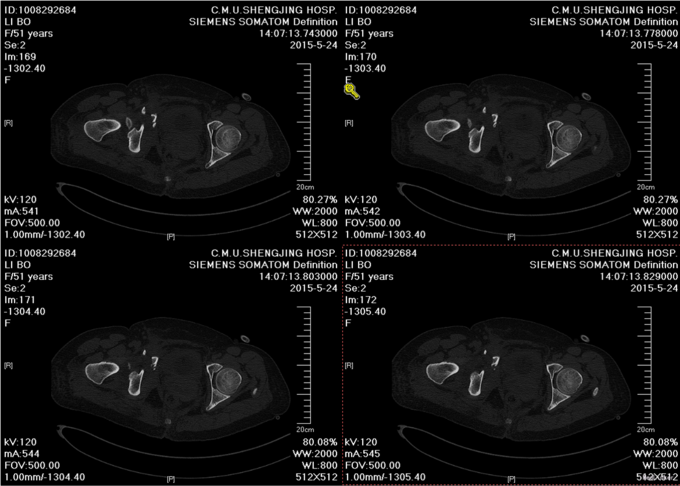

主诉:外伤后右髋部疼痛肿胀8天 现病史:患者于2015年5月16日发生车祸,伤后右髋部疼痛肿胀,下肢运动障碍,急诊120送至丹东市二医院,行骨盆平片,骨盆CT提示骨盆骨折,给予输血补液、骨牵引及留置尿管等对症治疗,急诊以“骨盆骨折”为主要诊断收入我科,患者病来无头晕头痛,无恶心呕吐,留置导尿中,大便正常。

诊断:骨盆骨折(Tile B1) 患者入院后完善检查后,全麻下行骨盆骨折切开复位钢板内固定术,术后给予抗炎,消肿,冷敷,患肢抬高等对症治疗。患者每天换药观察切口愈合情况,无红肿及渗出,待伤口14天后予以拆线治疗,予以出院,给予康复处方。